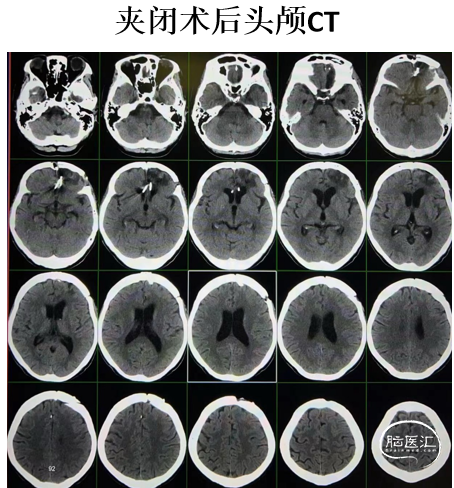

病例1

· 患者中年妇女。

· 4个月前因 “突发意识不清2小时”急诊入院。入院GCS评分5分。检查发现左大脑前动脉A2段动脉瘤破裂并蛛网膜下腔出血。在当地全麻下行左侧大脑前动脉A2动脉瘤破裂出血开颅夹闭+血肿清除+脑脊液漏修补术。术后恢复好。

3个月后复查DSA显示:动脉瘤复发

头颅CT

术前

术后第一天

4个月复查,停单抗

8个月复查

停单抗

1年半复查